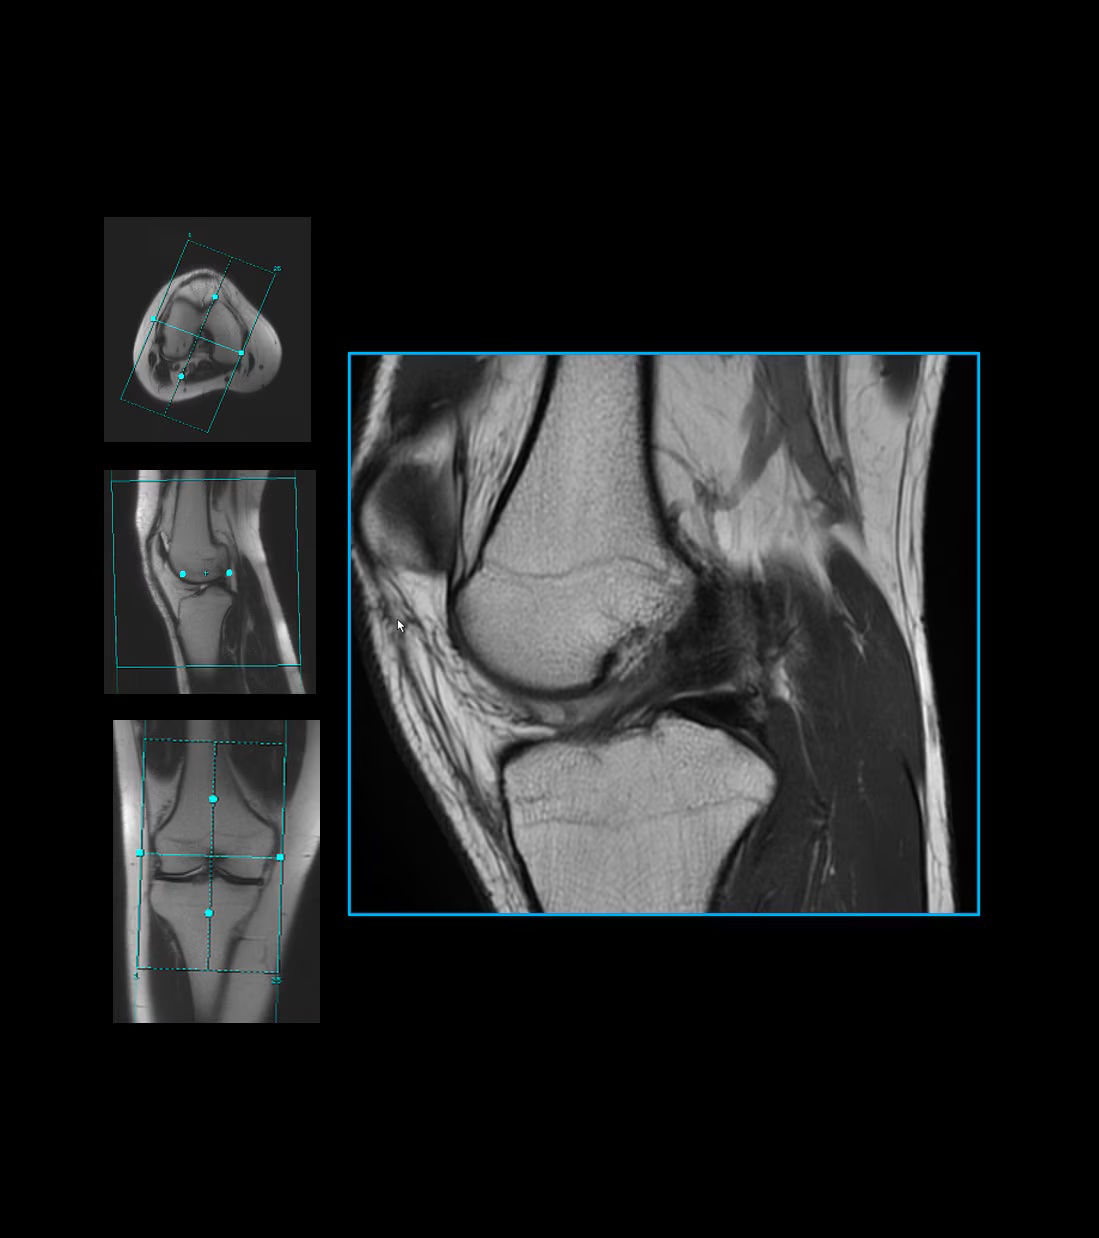

Simplifies scan setup with customized parameters

Optimizes uniformity, SNR and parallel imaging

Automatically selects which coils and elements to use

Automatically detect anatomy and prescribe slices based on the anatomical reference and orientation defined for the most commonly requested exams

Deliver consistent and quantifiable results regardless of pathology, patient position, time between scans and technologist variability

Save time by automating slice placements and avoid repeat scans